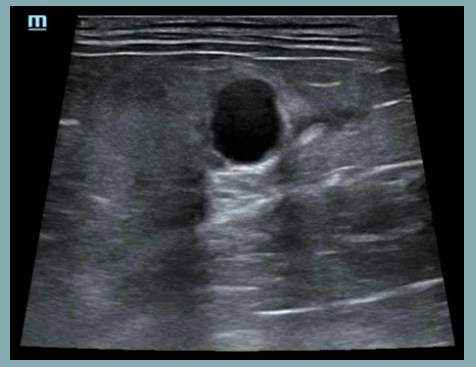

Artefactos: Sombra de borde

- Se forma en los bordes de estructuras curvas o redondeadas, como un quiste, un vaso sanguíneo o una lesión nodular.

- La imagen muestra una sombra longitudinal a cada lado del borde de la estructura redondeada, debido a la refracción de las ondas en el borde estructural.